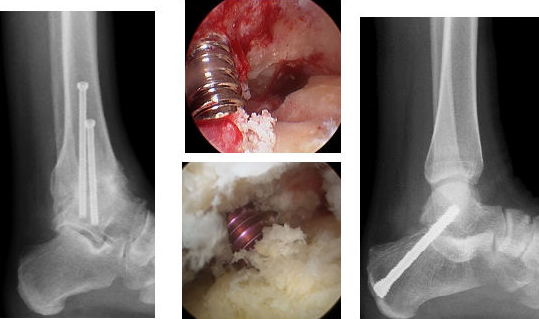

Auch die arthroskopische Versteifung des oberen Sprunggelenkes ist zu einem Routineverfahren geworden. Gerade bei diesem Problem kann am Röntgen sehr gut die schnelle knöcherne Heilung festgestellt werden.

Röntgenbilder und intraoperative Bilder des Schraubensetzens bei der Versteifung des oberen (links und Mitte oben)sowie des unteren Sprunggelenkes (Mitte unten und rechts)

Die arthroskopische Behandlung des unteren Sprunggelenkes wird v.a. bei einer Arthrose zur Durchführung einer arthroskopischen Versteifung des unteren Sprunggelenkes vorgenommen. Auch kann mittels dieser Technik ein symptomatischer zusätzlicher Knochen (os trigonum) an dieser Lokalisation arthroskopische vorgenommen werden.